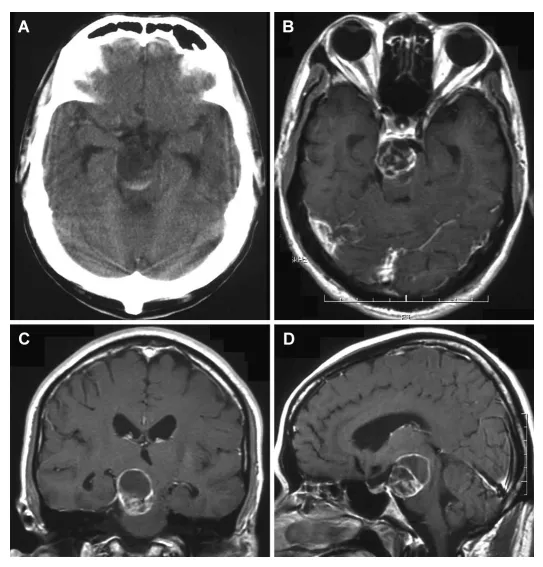

42岁男性因左侧偏瘫2周入院。头颅磁共振显示脑干旁异常病灶。查体见左侧轻偏瘫(徒手肌力测试4/5级),颅神经检查示右侧滑车神经麻痹及三叉神经第三支分布区感觉减退。全身系统检查无异常,无神经纤维瘤病皮肤表现。MRI显示脑外占位,T1加权像呈低信号,T2加权像呈高信号,增强扫描见脚间池内边界清晰的强化多囊性病灶,压迫脑干,肿瘤直径2.5厘米。

患者出院后拟2个月后手术。1个月后因左侧偏瘫加重急诊再入院。颅神经检查显示左侧偏瘫加重至2/5级,合并右侧动眼神经麻痹、滑车神经麻痹、三叉神经全分布区感觉减退及面瘫。CT及MRI显示肿瘤内出血,直径扩大至3.0厘米(图1)。

图1.A:平扫CT显示低密度肿块伴高密度区域,提示瘤内出血;B:轴位;C:冠状位;D:矢状位T1加权增强MRI,可见脚间池内边界清晰的强化多囊性病灶,压迫脑干。